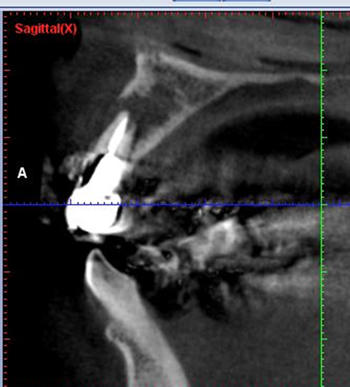

歯内療法には3次元的に診断できるのでCT検査は有効です。

CT検査で歯根破折はなく、病巣のみであれば抜歯しないで外科的歯内療法を行って歯を残せる可能性が高いです。